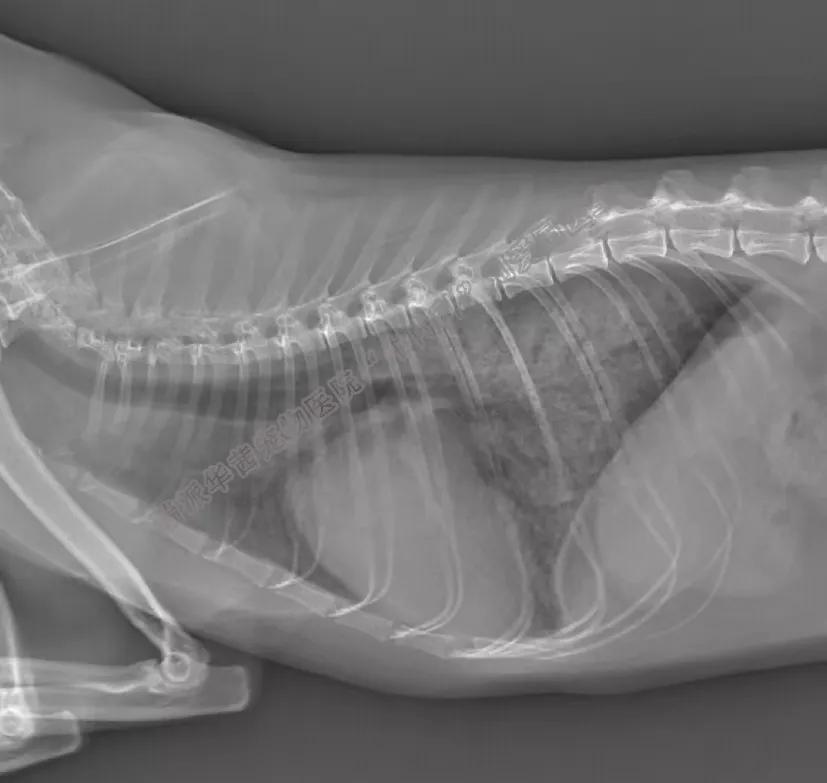

X光检查

心影正常或明显增大,呈典型的“爱心”型表现。因继发性房室瓣关闭不全而致心房增大、肺淤血、可能出现胸腔积液、可能因流出道狭窄压力差增大出现主动脉增宽。